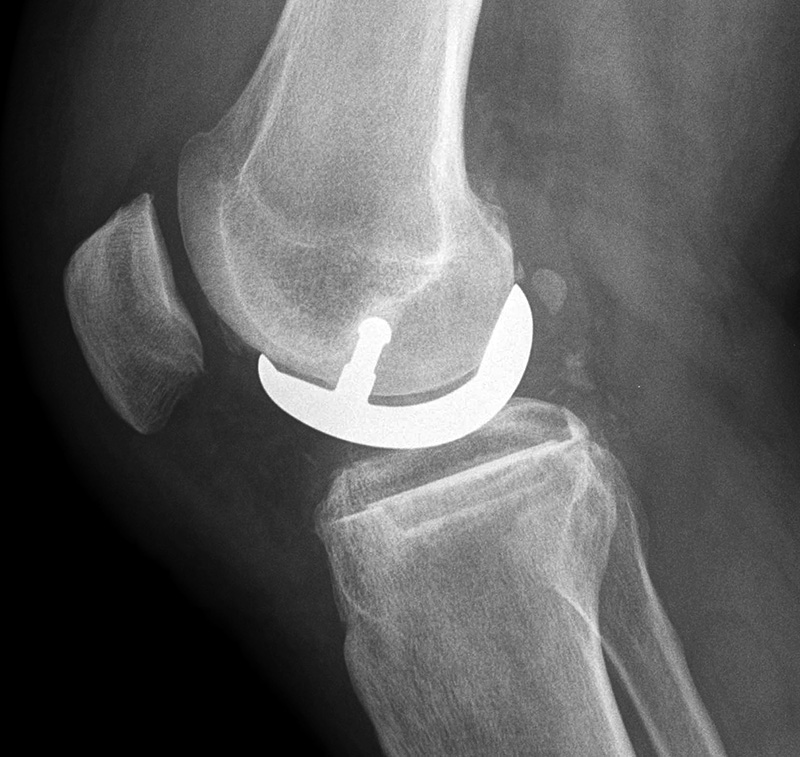

A PCL-retaining knee allows for preservation of the posterior cruciate ligament and is a relatively unconstrained design (figure: cruciate retaining TKA). For this type of prosthesis to be successful there must be good bone stock, intact surrounding muscles and ligaments, and a posterior cruciate ligament that remains functional (Mulcahy, 2013).

| Posterior cruciate retaining total knee arthroplasty (TKA) |

| Posterior cruciate retaining total knee prosthesis with cementless femoral and cemented tibial component and patellar resurfacing |

Unicompartmental knee prosthesis placed in the medial compartment (lateral view) |